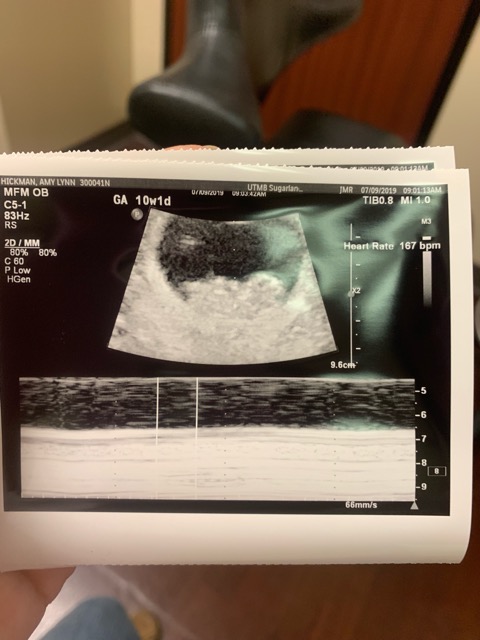

Hey ladies! I just had an ultrasound done today at 10w1d. I have my early gender blood test in two weeks so until then let’s have fun guessing! My little beans heart was beating at 167 bpm